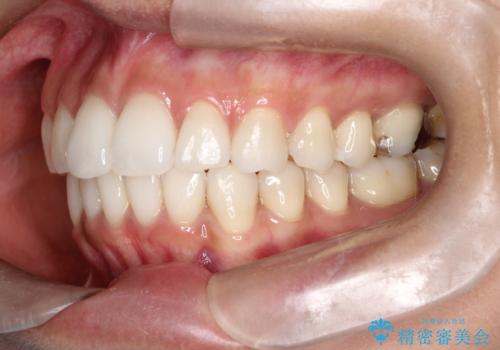

【インビザライン】前歯の凸凹をIPRで改善

- 前歯の凸凹を主訴に来院されました。

前歯を並べるために歯と歯の間にヤスリを入れてわずかに歯を削ることでスペースを確保しています。

歯と歯の間にヤスリを入れてわずかに歯を削ることでスペースを確保する処置をIPRと呼びます。

当院では拡大鏡を用いて丁寧に処置することで歯冠形態を損なわずに行うことができます。